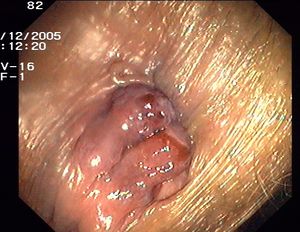

يقال للباسور إنه من الدرجة الأولى إذا بقي داخل الشرج، ويصير درجة ثانية إذا ظهر للخارج وعاد من نفسه، ويتطور ليصير درجة ثالثة إذا خرج ولم يعد إلا بوساطة المريض أو الطبيب، أما الدرجة الرابعة فإنه يستحيل فيها إعادة الباسور للداخل.

1- البواسير الداخلية: تنشأ داخل القناة الشرجية في الغشاء المخاطي وهي توسعات وعائية في نهاية الأوعية الباسورية، تتبارز بشكل كتلة صغيرة داخل الشرج، قد تتدلى تدريجياً نحو الأسفل فتصبح البواسير داخلية وخارجية في آن واحد.

- الأوعية الدمويّة المنتفخة تندفع إلى الخارج تلقائيًّا دون وجود مُسبب لذلك لكن المريض يستطيع إرجاعها إلى الداخل بواسطة اليدّ وقد يتزامن معها النزيف.

- الأوعية الدمويّة المنتفخة تندفع إلى الخارج وتبقى كذلك ولا يستطيع المريض إرجاعها إلى الداخل أبدًا بأي وسيلةٍ.